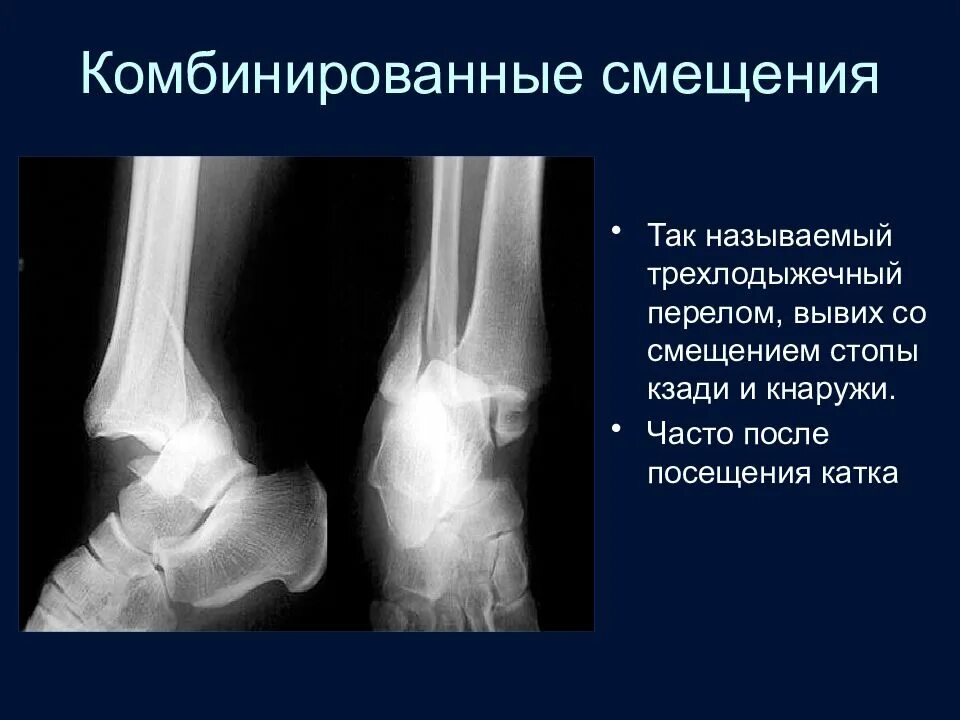

Вывих со смещением